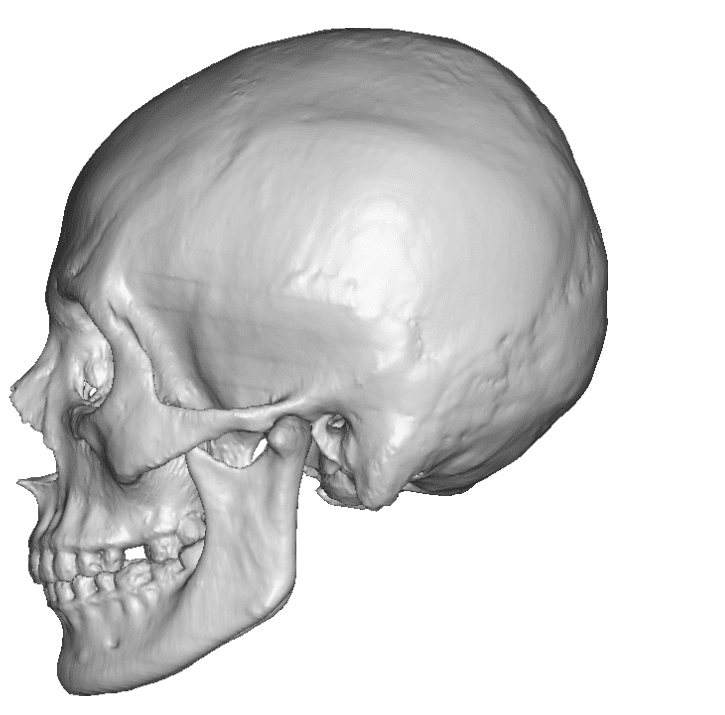

Desire for rounder shape to the top of the head from a congenital parasagittal deficiency skull shape.

Custom skull implant designed to fill in the parasagittal deficiencies.

Desire for rounder shape to the top of the head from a congenital parasagittal deficiency skull shape.

Custom skull implant designed to fill in the parasagittal deficiencies.